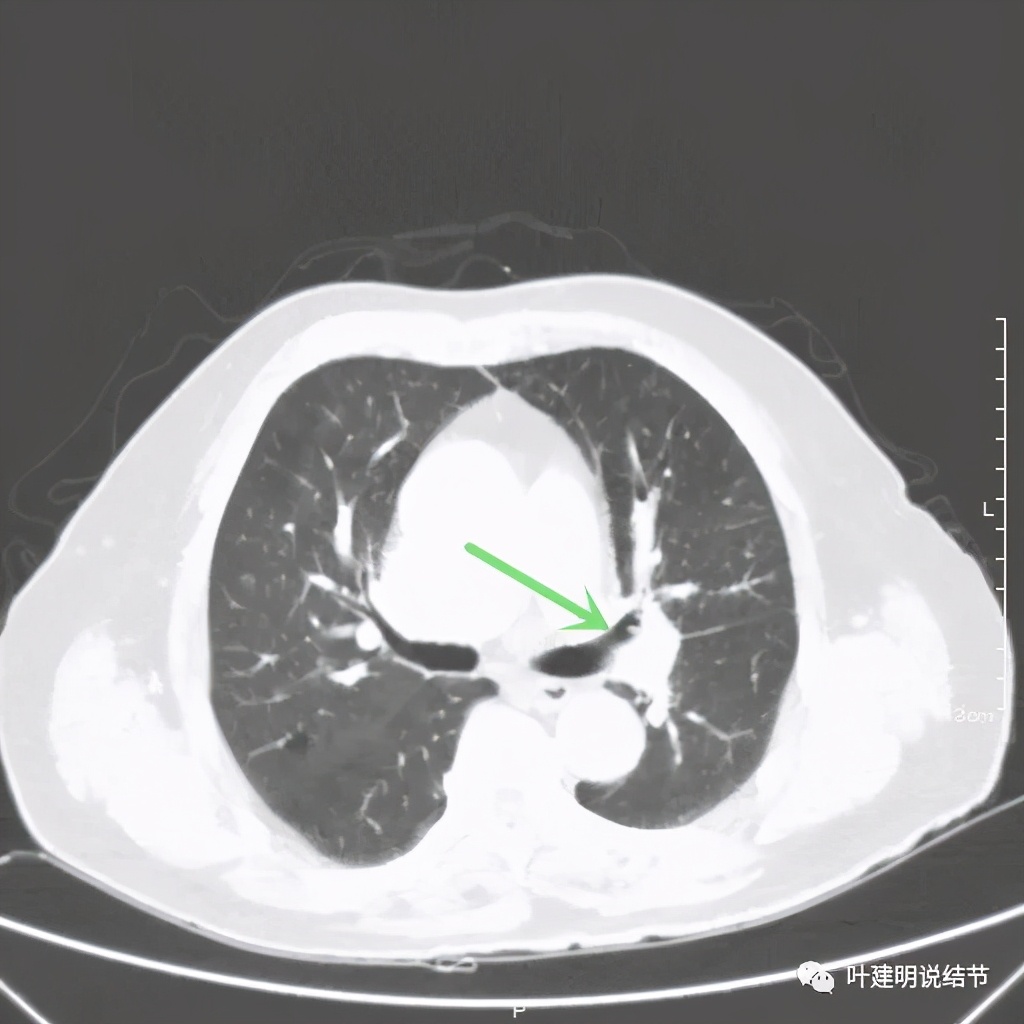

左上肺基本已经不见肿瘤,只在主动脉旁少许软组织影

上图示主动脉弓水平仍见软组织影